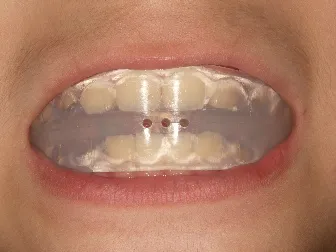

治療中➁拡大・前歯の並替え装置(写真はイメージ)

QH

BH

ブラケット

トイシャー本体

ヘッドギアー